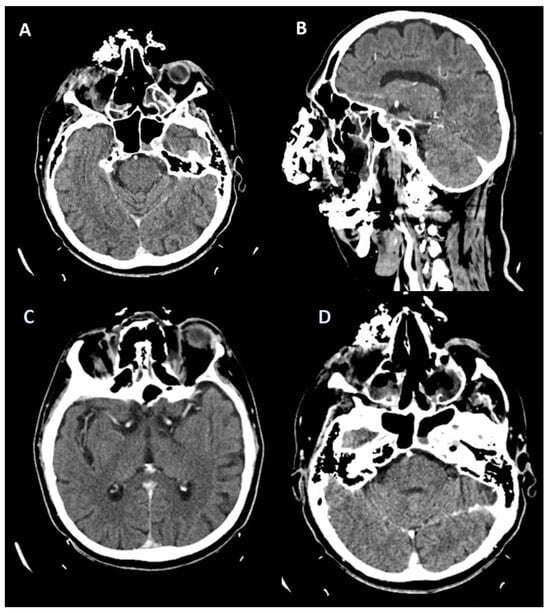

2.1. Case 1

2.2. Case 2

2.3. Case 3